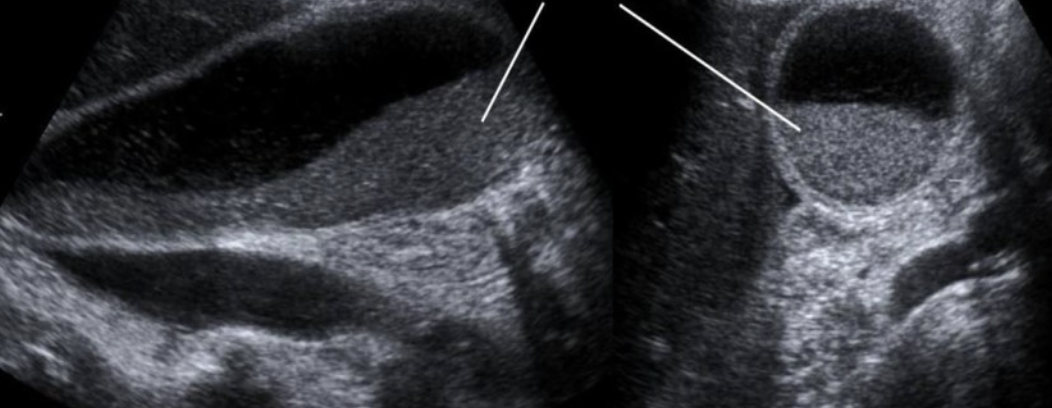

Hydronephrosis → dilation of renal collecting system from mechanical obstruction or functional dysfunction (calculi, mass, trauma, pregnancy)

2D US: grade 1 (mild) → pelviectasis, cortex preserved, grade 2 (mild to moderate) → expands into major calyces, cortex preserved, grade 3 (moderate) → expand all calyces, entire pelvis dilated, cortex preserved, grade 4 (severe) → cortical thinning, AKI to CKD, creatinine >1.2